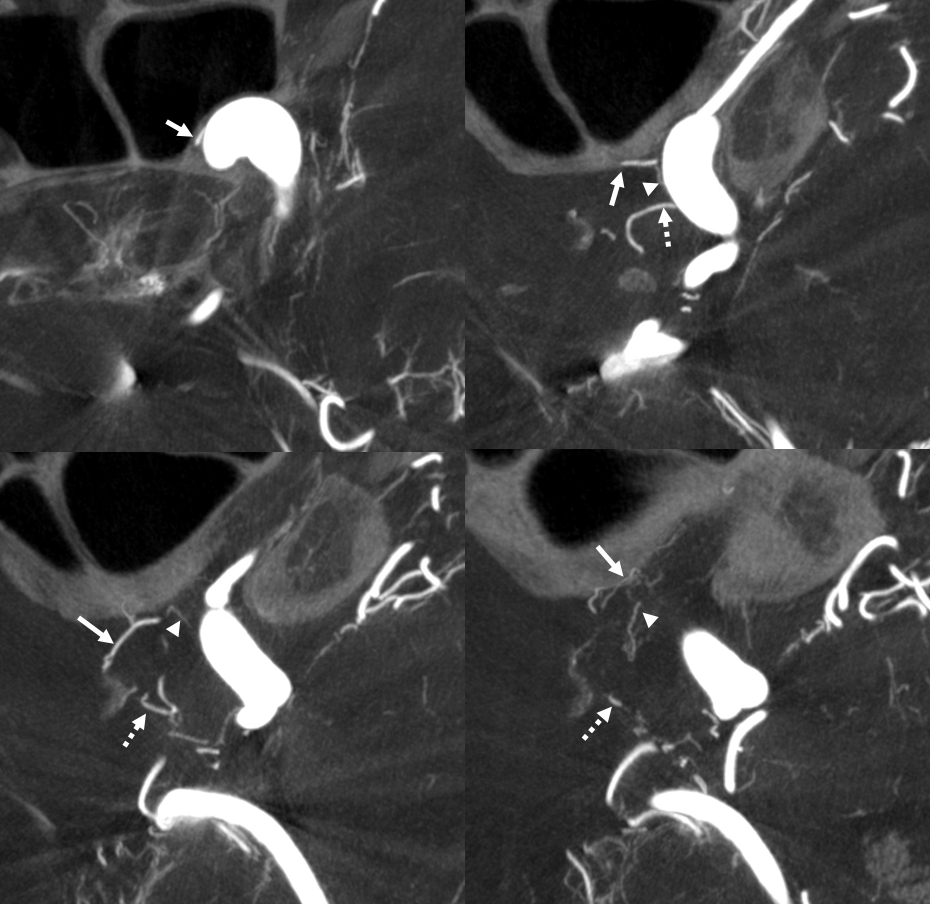

What supplies the bulk of optic nerve? Central Retinal artery is for the distal portion of nerve and retina. What about the rest — intracranial, intracanalicular, proximal intraconal segments? The answer is not clear (let me know if you do), but i believe the bulk of it comes from the superior hypophyseals. It is probably in balance with the recurrent branch of the central retinal artery. Below is an example of an especially prominent proximal-most superior hypophyseal (arrows) supplying the pituitary stalks and optic nerve in the canalicular and intracranial locations. Note how well one can see the branch in coronal view (bottom left image). In this case there are two large superior hypophyseals — the more distal one (dashed arrows) supplies predominantly the pituitary stalk. The inferior hypophyseal artery is marked by arrowhead. Lower right image is coronal.

Movie is the best way

Here too superior hypophyseal (arrow) supply of the intracranial optic nerve (oval) and possibly chiasm is shown definitively (lower right image is coronal)

Pattern of optic apparatus supply and unusual hypophyseal ILT vessel

VR — the anterior-most branch of the superior hypophyseals is usually the largest (arrow). The others are too small to see on a VR image

MIPS. The anterior, proximal-most branch (arrow) tends to supply the optic nerve (white oval), while the more posterior branches (dashed arrows), when present, supply more posterior structures such as chiasm and tract (dashed oval)

A highly unusual branch originating from ILT region swings underneath the cavernous ICA and supplies the floor of the pituitary fossa. Yet unknown, as far as i know